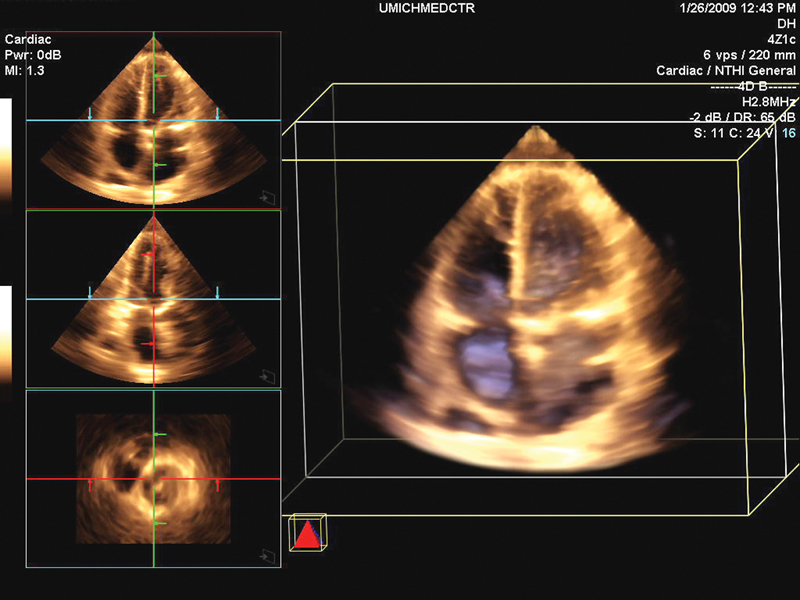

فحوصات تشخيصية لبعض امراض القلب والشرايين التاجية